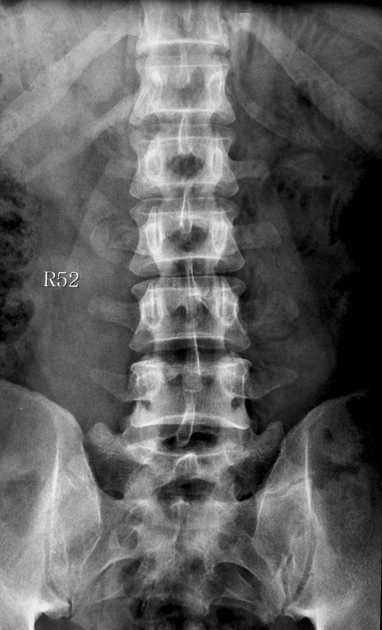

spondylolisthesis

forward movement vertebra on another, most common at L5-S1, due to spondylosis of pars or severe osteoarthritis

spondylolysis (lumbar)

separation of pars interarticularis (neck), most common at L4-5